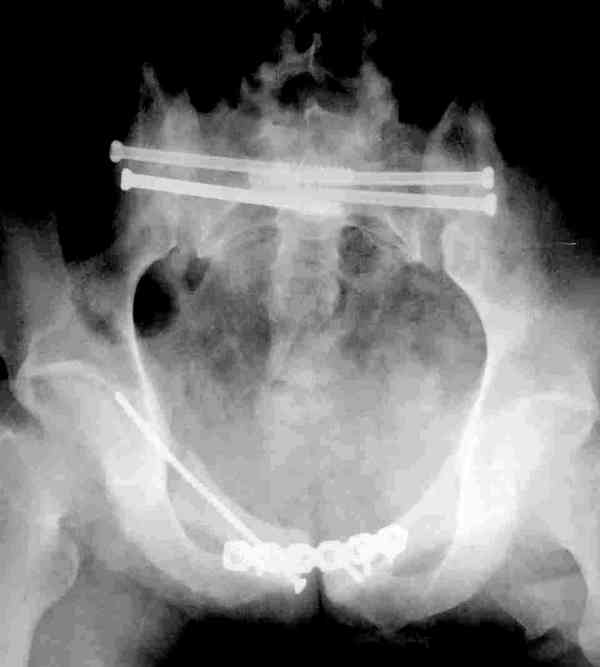

Коллеги, как и когда вы бы разрешили нагрузку в такой ситуации.

Молодой парень, без соматики. Сейчас чуть больше 2-х нед после операции,

швы сняты, мочится сам. Был тяжелый, после операции дней 10 пытался

выполнить лежа поперечный шпагат (успешно, так и лежал большей частью,

может быть из-за обширной гематомы промежности). Репозиция не

идеальная, но фиксация довольно надежная, за 2 нед ничего не

разъехалось". Сейчас пришел в ум. Когда, по-вашему, можно дать нагрузку,

и на какую ногу, или на обе? Или вообще подскажете

программу реабилитации.

PS Заранее извиняюсь за качество снимков, до не делали (body scan),

если не видно - то - полные разрывы КПС с двух сторон. после КТ

сломался. Неврологии вроде бы нет.